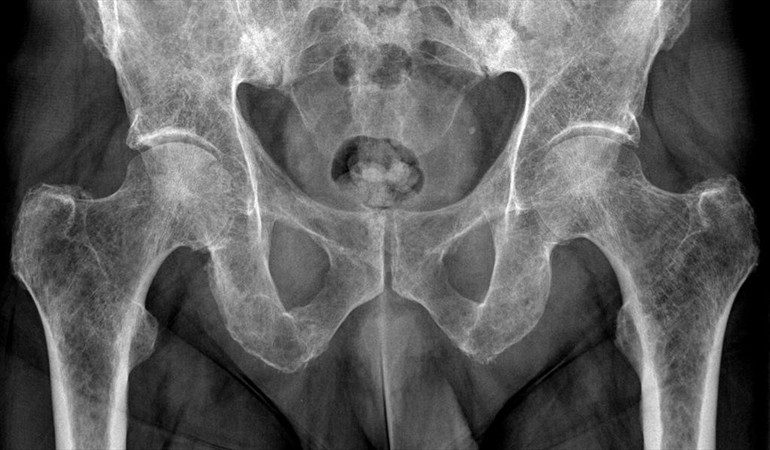

Al revisarlo, no tenía ningún problema visible. Fue allí cuando el hombre les dijo a los especialistas que sentía malestar en su genital, por lo que se le tomó una radiografía pélvica.

Ahí supo que su pene se estaba osificando, es decir convirtiendo en hueso, según informaron los medios internacionales y consignó Radio ADN.